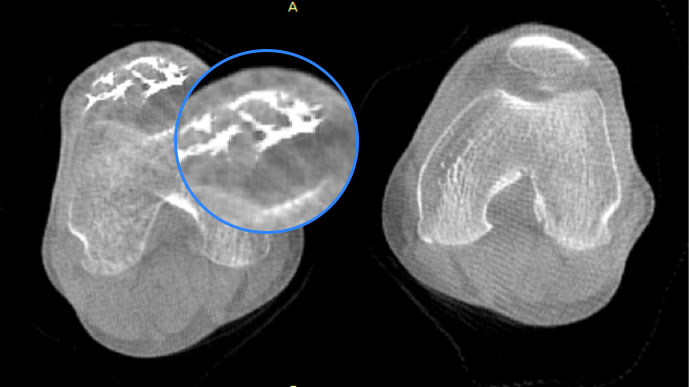

膝關節